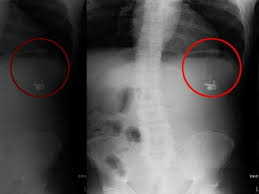

৩০ বছর পর এক ব্যক্তির পেট থেকে বের করা হলো সিগারেটে আগুন ধরানোর লাইটার। জরুরি গ্যাস্ট্রোস্কোপি করার পর চিকিৎসকরা ওই ব্যক্তির পেটে একটি ঘনক আকৃতির বস্তু দেখতে পান, যার গঠন পাকস্থলীর অ্যাসিডে বিকৃত হয়ে গিয়েছিল।

বস্তুটি যে একটি লাইটার তা নিশ্চিত হওয়ার পর চিকিৎসকরা এটি অপসারণের একটি কৌশল নির্ধারণ করেন। লাইটারটিকে ঘিরে ধরে সফলভাবে বাইরে বের করে আনা হয়।

যদিও পাকস্থলীর অ্যাসিডে লাইটারটির বাইরের অংশ ক্ষতিগ্রস্ত হয়েছিল, তবুও এর ভেতরে গ্যাস ছিল—এবং চিকিৎসকদের বিস্ময়ের বিষয়, লাইটারটি তখনও সচল ছিল! সূত্র- সামা